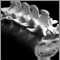

A lumbosacral spine CT is a computed topography scan of the lower spine and surrounding tissues.

CT rapidly creates detailed pictures of the body. A CT of the lumbosacral spine is an excellent tool for evaluating fractures and degenerative changes of the spine, such as those due to arthritis.